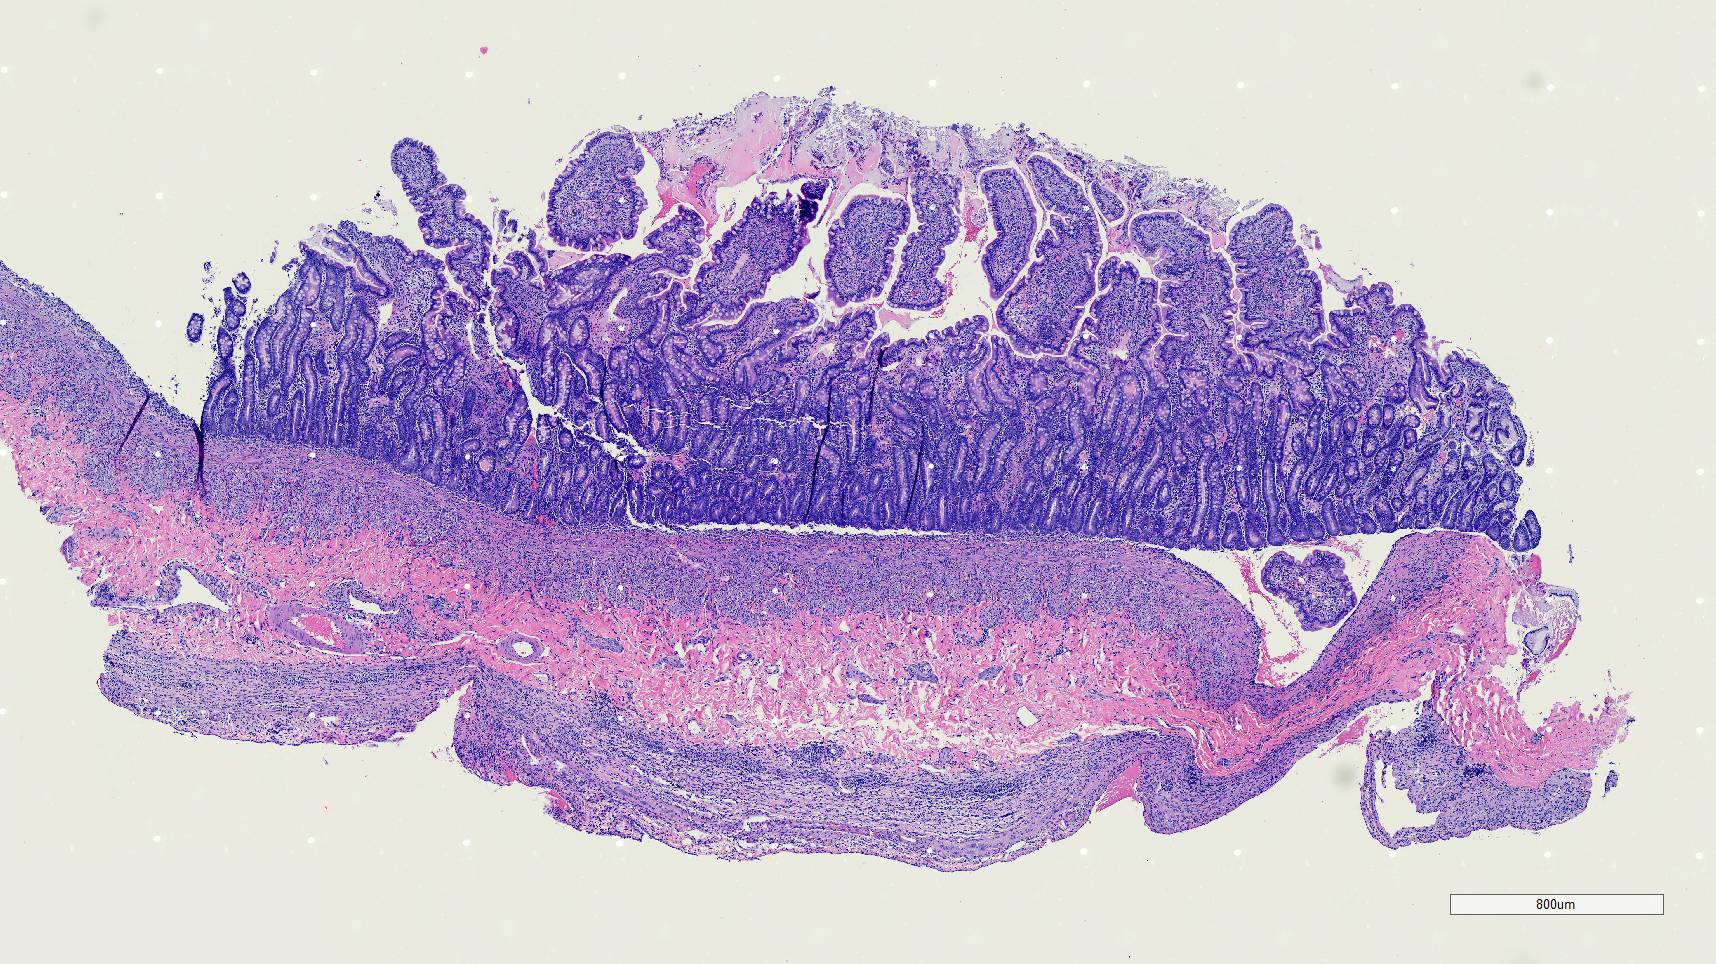

Microscopic Description:

Duodenum, jejunum and ileum: Diffusely throughout the sections, there is partial to complete loss of the leiomyocytes of the outer and inner muscularis, which are multifocally replaced by loose fibrous connective tissue (fibrosis). The remaining smooth muscle is infiltrated by large numbers small and intermediate lymphocytes, few macrophages and neutrophils. The same inflammatory infiltrate is present throughout the muscularis mucosae. Remaining leiomyocytes have pale, frequently vacuolated cytoplasm. In the submucosa, muscularis and serosa there are small to moderate numbers of perivascular lymphocytes. Small lymphocytes, and infrequently neutrophils, surround or infiltrate the myenteric and submucosal ganglia, though neurons do not exhibit degenerative changes. The lamina propria contains a markedly increased number of lymphocytes, plasma cells and a mildly increased number of eosinophils. The epithelium is diffusely overlain by myriad bacterial rods. The serosa is mildly expanded by increased clear space (edema) and is lined multifocally by markedly hypertophied mesothelium. In the stomach a similar process is observed but restricted to the outer aspect of the muscularis with a patchy/multifocal distribution and sparing of the muscularis mucosae. (section not submitted).

Duodenum, jejunum and ileum: Severe, diffuse, chronic lymphocytic leiomyositis with severe muscularis atrophy; marked, diffuse, chronic lymphoplasmacytic enteritis.

Small intestine: Leiomyositis, lymphocytic, chronic, diffuse, severe, with marked smooth muscle loss and fibrosis.